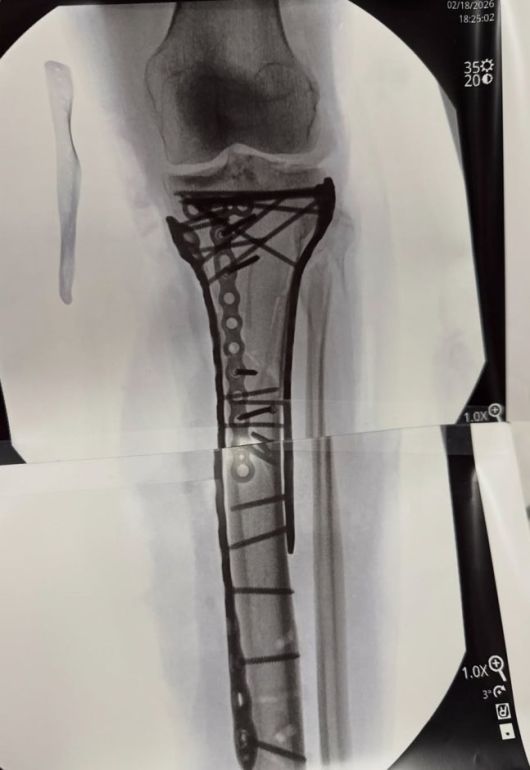

이탈리아에서만 네 번의 수술을 받을 만큼 힘든 시간을 보낸 그는 미국으로 이송돼 다섯 번째 수술까지 받았다. 본은 그동안 왼쪽 경골 복합 골절에 비골 골절 수술을 받았고, 오른쪽 발목 골절 수술도 받았다. 여기에 혈액이 고이는 구획증후군과 낮은 헤모글로빈 수치 등으로 큰 위기를 겪었다. 일각에서는 다리를 절단할 수 있다는 암울한 예상도 적지 않았다.